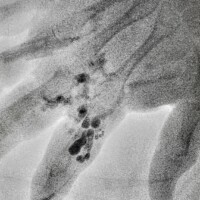

Veins are blood vessels that carry blood from organs back into the heart and lungs for re-oxygenation. Under normal circumstances, venous circulation is a low-pressure system. Malformations affecting the venous circulation are, by far, the most common comprising nearly 75% of all vascular malformations. Venous malformations can either be isolated or part of a syndrome, most commonly Klippel-Trenaunay Syndrome. The cause is unknown although certain genetic mutations have been identified in patients with these malformations. Venous malformations can either be an isolated event in an individual sporadically or inherited from parents in a familial form. They are present at birth but do not become apparent until later in life when an external or internal stimulus such as activity, injury, puberty, pregnancy, surgery, etc. triggers symptomatic exacerbation of the malformation. They can happen anywhere in the body at any depth. Symptoms range from minor aches and pains to recurrent, life-threatening hemorrhage, clotting disorders, and organ damage, mostly within bones, joints, and skeletal muscles.

These lesions are readily identified on properly conducted MRI studies. Treatment primarily consists of Direct Stick Embolization under ultrasound or x-ray. This treatment is generally well-tolerated if performed judiciously with focal treatments performed in multiple sessions dispersed over several sessions with appropriate length intervals in between sessions. Aggressive treatment of large areas can cause local skin and nerve damage, and heart and lung related problems.